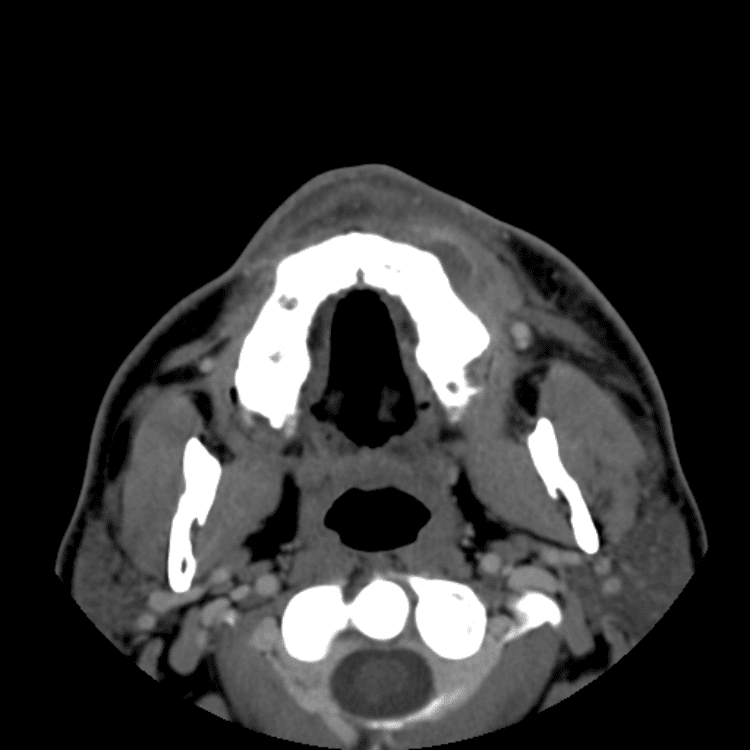

Head and Neck

Practice

Simulates call by including subtle or difficult cases and some normals.

27 cases